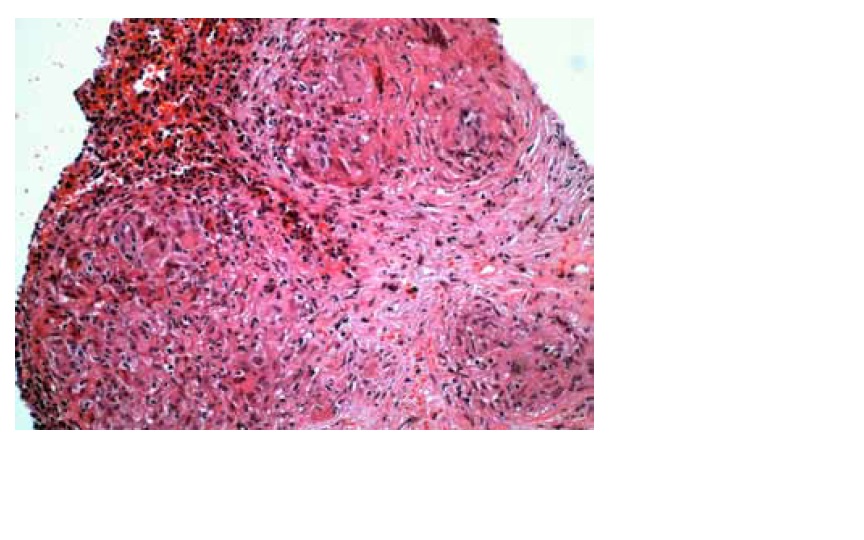

Radiografia torácica revelou aumento de volume e densidade hilar direita com esboço de nodulação. A TAC toracoabdominal demonstrou m&uac...